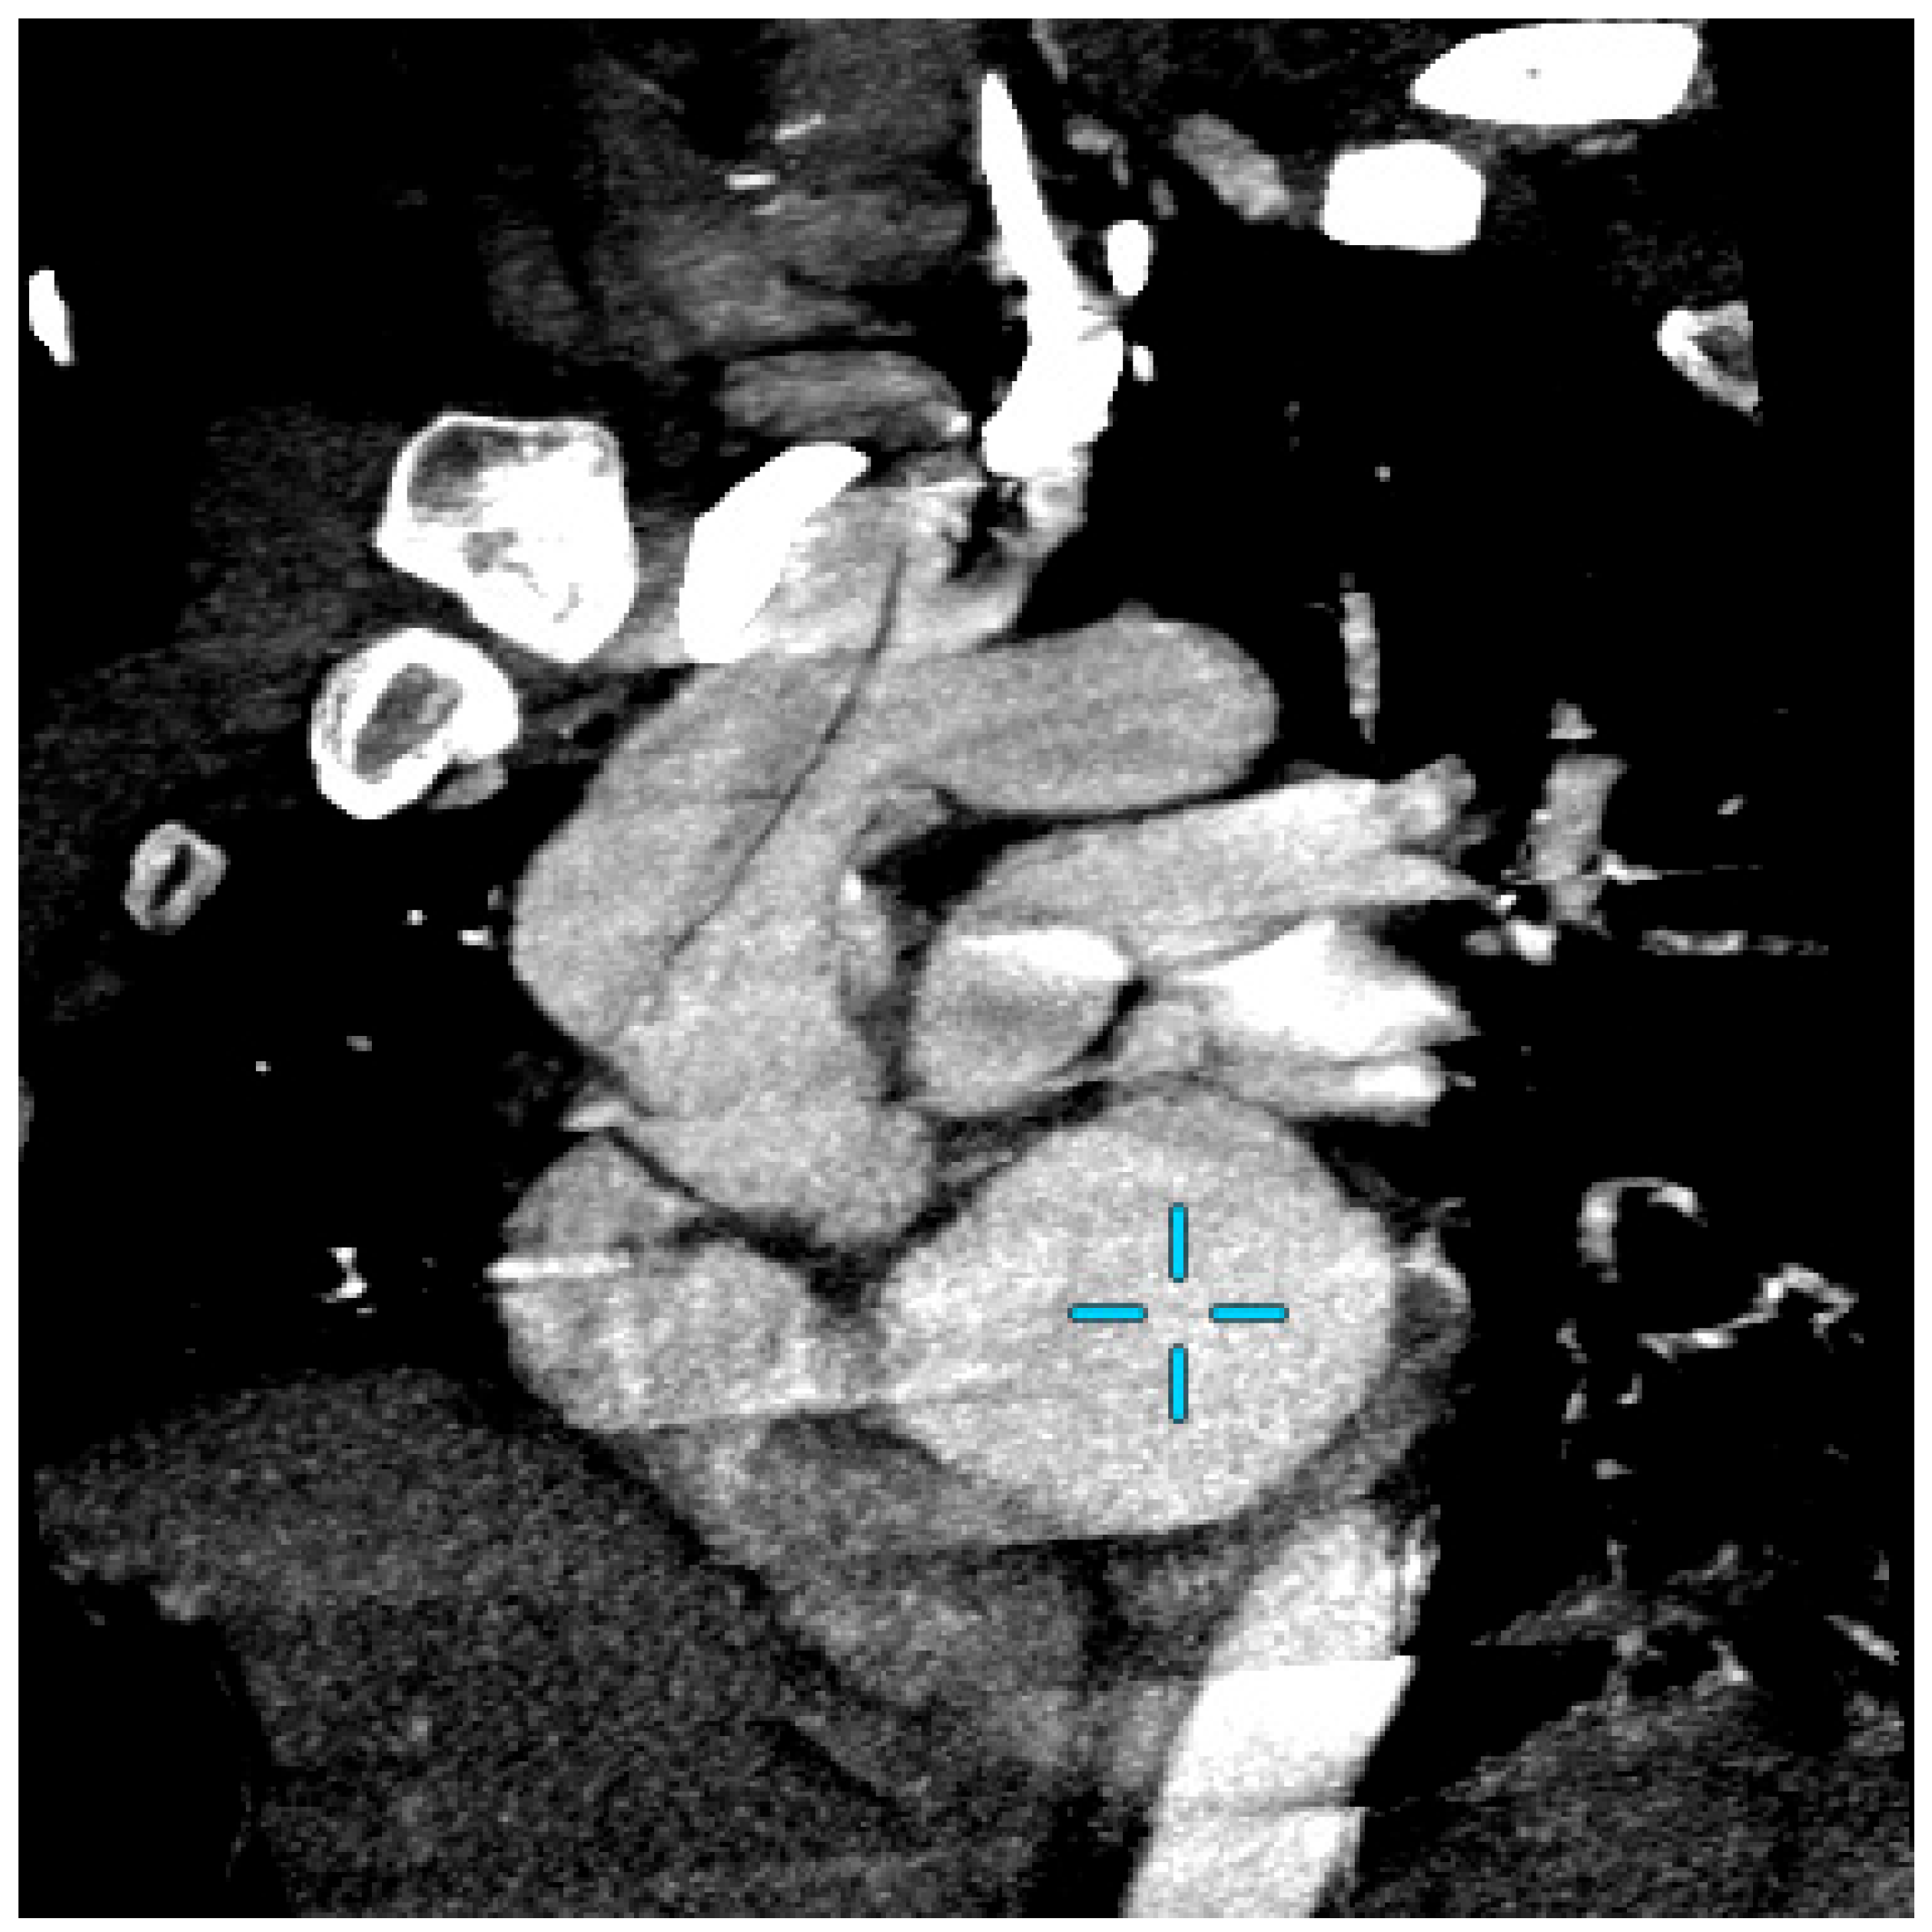

Computed tomography angiography (CTA) excluded a recurrent aortic dissection and showed a residual valve opposite the brachiocephalic trunk without extension or residual aneurysm, which was unchanged from the results of a CTA scan carried out 5 years earlier (Figure 1).

Figure 1.

Computed tomography angiography (CTA) of aortic arch on emergency with “candy cane” aspect. The blue cross show the left ventricule.